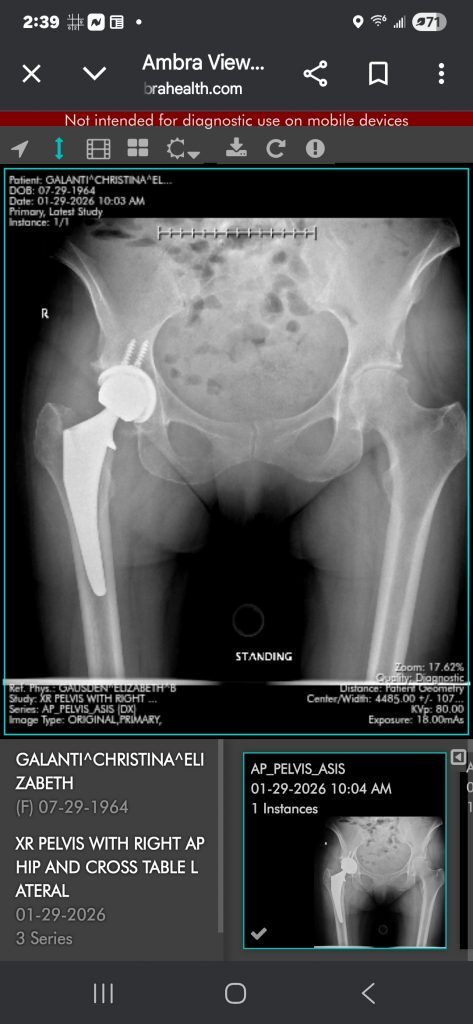

Dr. Gausden and her team are the best! Before my surgery, I couldn't straighten my right leg, walk any long distances, or climb stairs. I had pain all the time. I had my surgery on 1/2/26. Immediately after, I was able to stand straight, walk, and climb the stairs. My leg is straight for the first time in over 2 years!